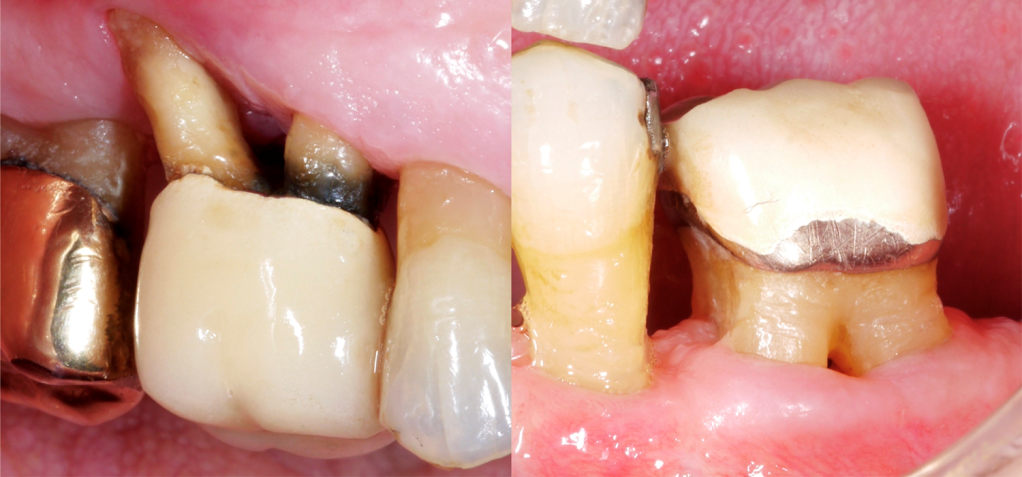

The loss of bone is specific to the branching of the roots of the tooth and is called a furcation defect. Since only teeth that have multiple roots suffer this, it usually only affects both the molar and the premolar teeth that are situated near the mouth back.

For more advanced cases, you may see a defect even without probes. This happens when the tissue surrounding the gums gets recessed, which means lowered on the root surfacing of the tooth, exposing the root that’s damaged as well.